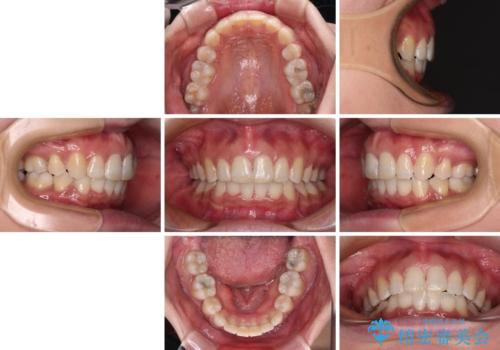

インビザラインが続けられない ワイヤー装置による抜歯矯正

- 上の前歯の飛び出した感じと上下前歯のデコボコを気にして来院された患者様です。

叢生が強く、口元の突出感もあるため、上顎左右第一小臼歯4本を抜歯することとしました。

2年ほどインビザラインを使用しましたが、どうしても歯の移動がマウスピースに追随せず、全顎ワイヤー矯正へ切り替えました。

ワイヤー装着後は2年弱で、しっかりと仕上げることができました。